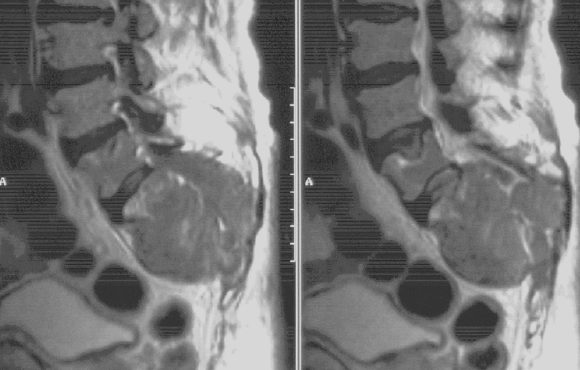

MM Steißbein

MRT mit einem multiplen Myelom mit Steißbeinauftreibung.